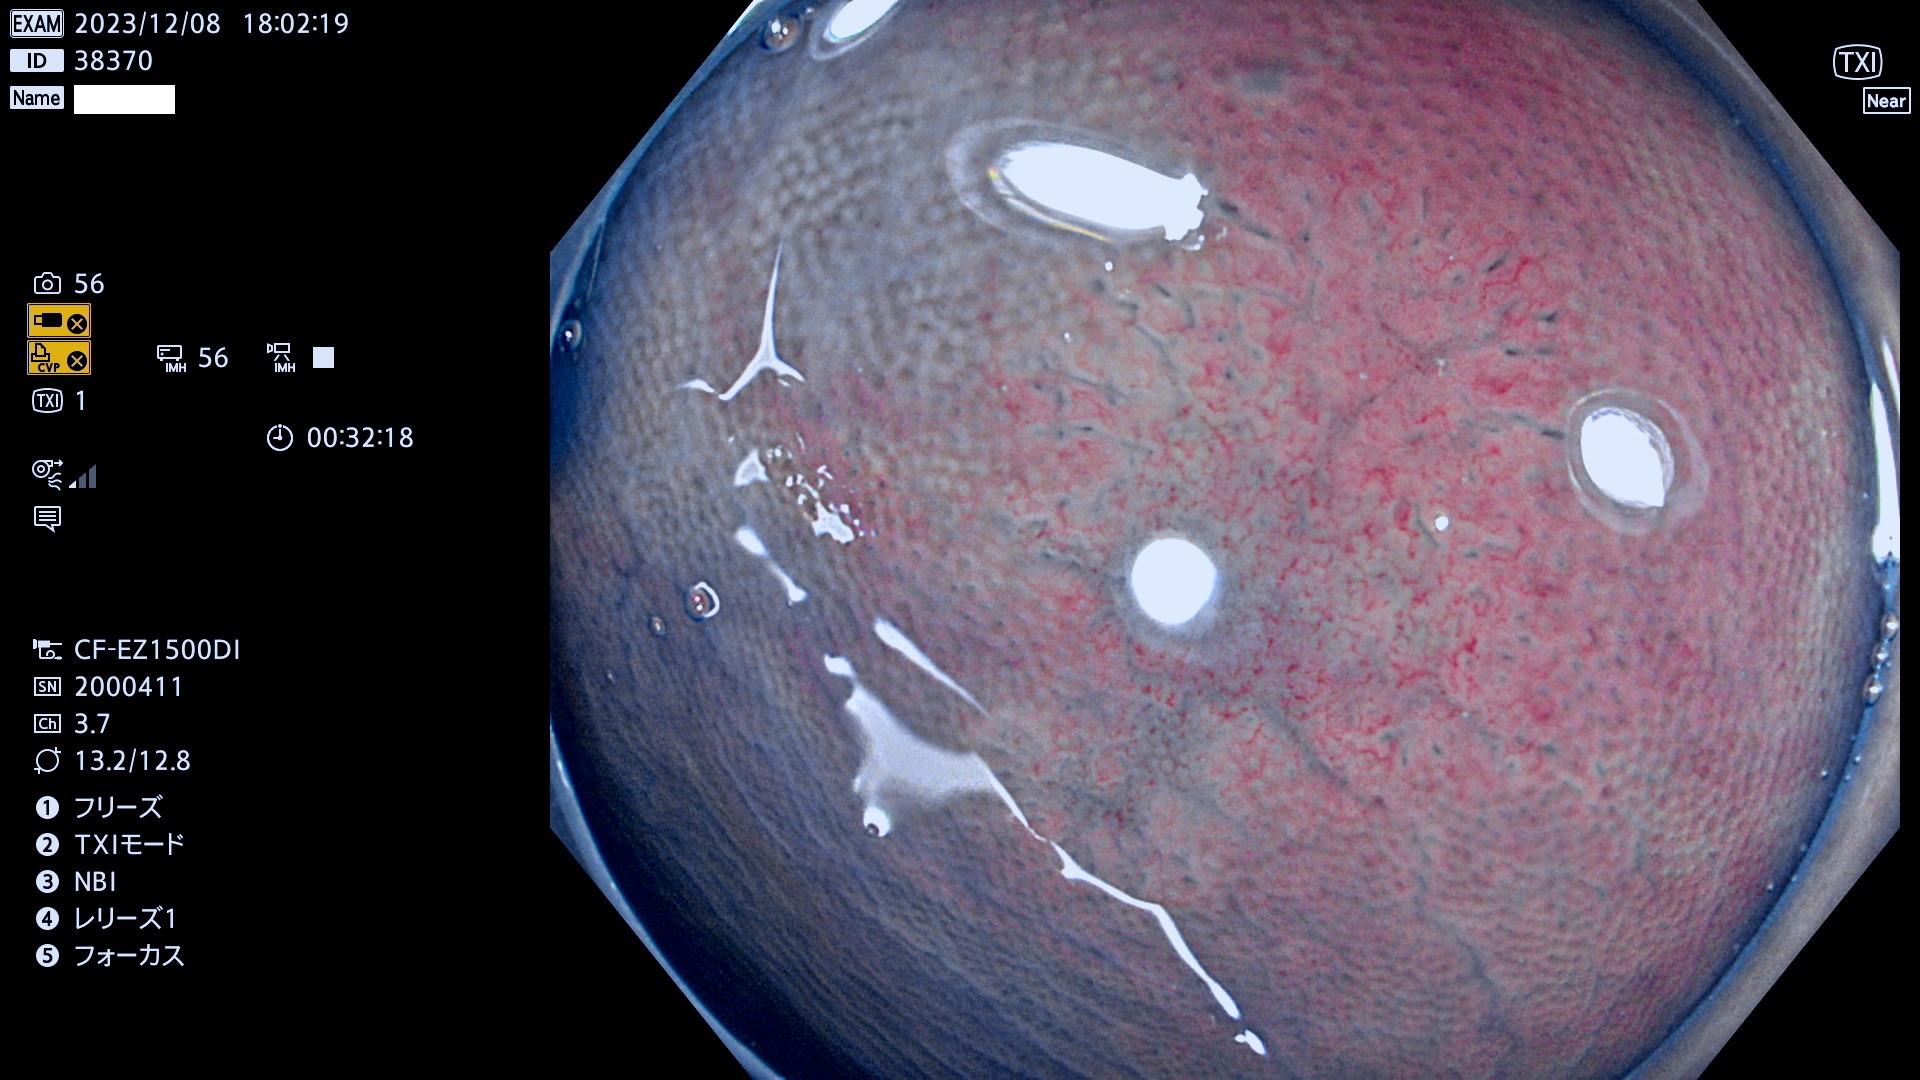

今週のUb、Uc型腺腫

表面型腺腫(Flat Adenoma)の中で、完全に平坦な物をUb、陥凹している物をUcと呼びます。平坦隆起型(Ua)よりも、発見が難しく危険な病変です。このタイプは「内視鏡後・大腸癌の重要犯人」であり、この発見率は「腺腫発見率」よりも、重要な意味があります。

毎週の検査(木・金・土・日)に発見されたUb、Uc型・腺腫を、その週の日曜の夜にUPし1週間、提示します。

抽出の対象期間 2023年12月7日(木)〜12月10(日)の4日間(48件の検査)12件